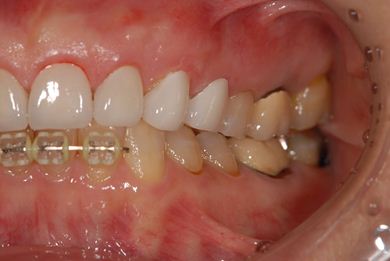

部分矯正治療+セラミック治療

| 性別/年齢 | 女性 / 54歳 | ||||||||||||||||||||||||||||||||

| 主訴 | 下の前歯のゆがみが気になり、相談。 | ||||||||||||||||||||||||||||||||

| 治療方針 | 上顎前歯の叢生を部分矯正にて審美的回復を行い、上顎前歯はラミネートベニアにて審美的回復を行う。 | ||||||||||||||||||||||||||||||||

| 治療内容 | 唇側部分矯正(ホワイト)、オールセラミックラミネートベニア8本 | ||||||||||||||||||||||||||||||||